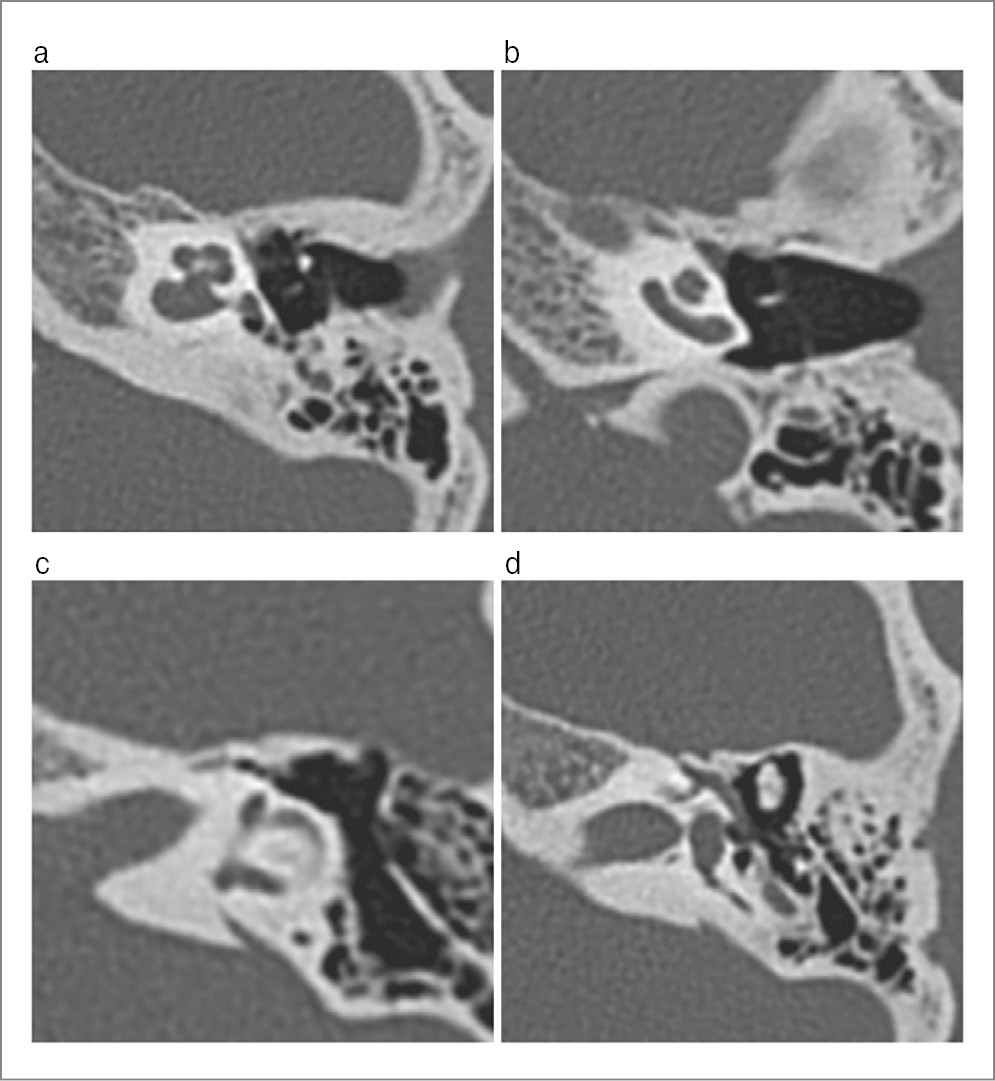

In March 2023, patient L., 24 years old, presented at the St. Petersburg Research Institute of ENT with hearing loss in both ears, more on the left, and periodic mixed tinnitus. She had these symptoms for 2 years. According to the patient, she had no previous history of chronic or acute ear diseases; her family history is unremarkable. From 2010 to 2016, she was followed up by an epileptologist for an epilepsy episode; in 2016, she was withdrawn from the follow-up. Somatically, she had an arach-noid retrocerebellar cyst and a congenital anomaly of the urinary system, left kidney duplication. Other findings were unremarkable. The otoscopic pattern was normal. When conducting acoustic impedance measurement, the type A tympanogram on both sides was recorded; the stapedial reflex-es on both sides were absent. Tonal audiometry corresponded to a grade 2 mixed hearing loss on the left, with the Carhart notch at 2000 Hz and grade 1 conductive hearing loss on the right (Fig. 1). When examined with a 128 Hz tuning fork, the lateralization of sound in the Weber test spread to the left ear, the Rinne’s, Federicci’s and Gellé tests were negative on both sides. CT (Fig. 2, 3) and virtual CT endoscopy of the ME (Fig. 4) showed no changes in the ME and IE. The configuration of the semicircular canals, the vestibular aqueduct, and the perilymphatic duct were unremarkable. TB CT showed no demineralization of the labyrinth bone capsule, gross deformations of the AO chain, or abnormalities in the structure of the ME and IE.

Fig. 3. MSCT scans of the left TB showed the normal structures of the IE and ME: a – normal dimensions and absence of the bone capsule defects in the posterior semicircular canal; b – normal dimensions and absence of bone capsule defects in the lateral semi-circular canal; c – normal dimensions and absence of bone capsule defects in the superior semicircular canal; d – normal dimen-sions and absence of defects in the IAC wall.